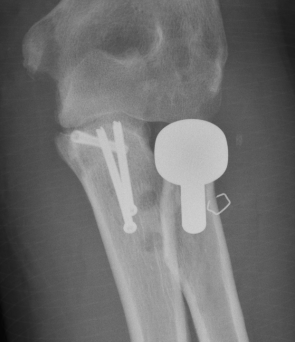

rh orif Radial Head Replacement Lateral

Radial head replacement with lag screw fixation of Type II coronoid

terribleterribleterribleterrible

Radial head replacement with lasso fixation of small coronoid fragment